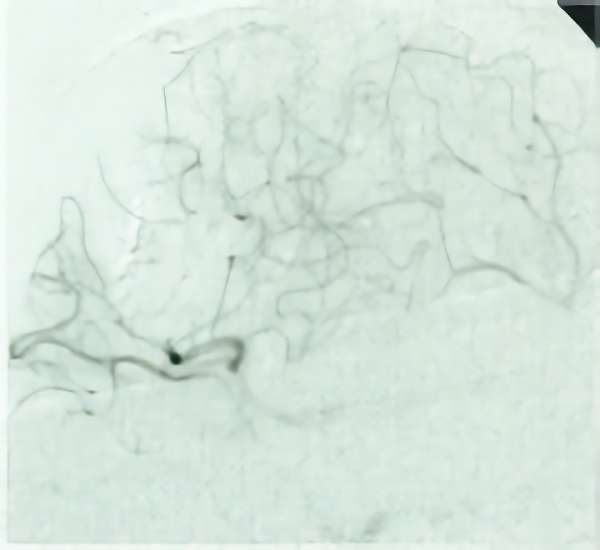

脳血管撮影

手術前